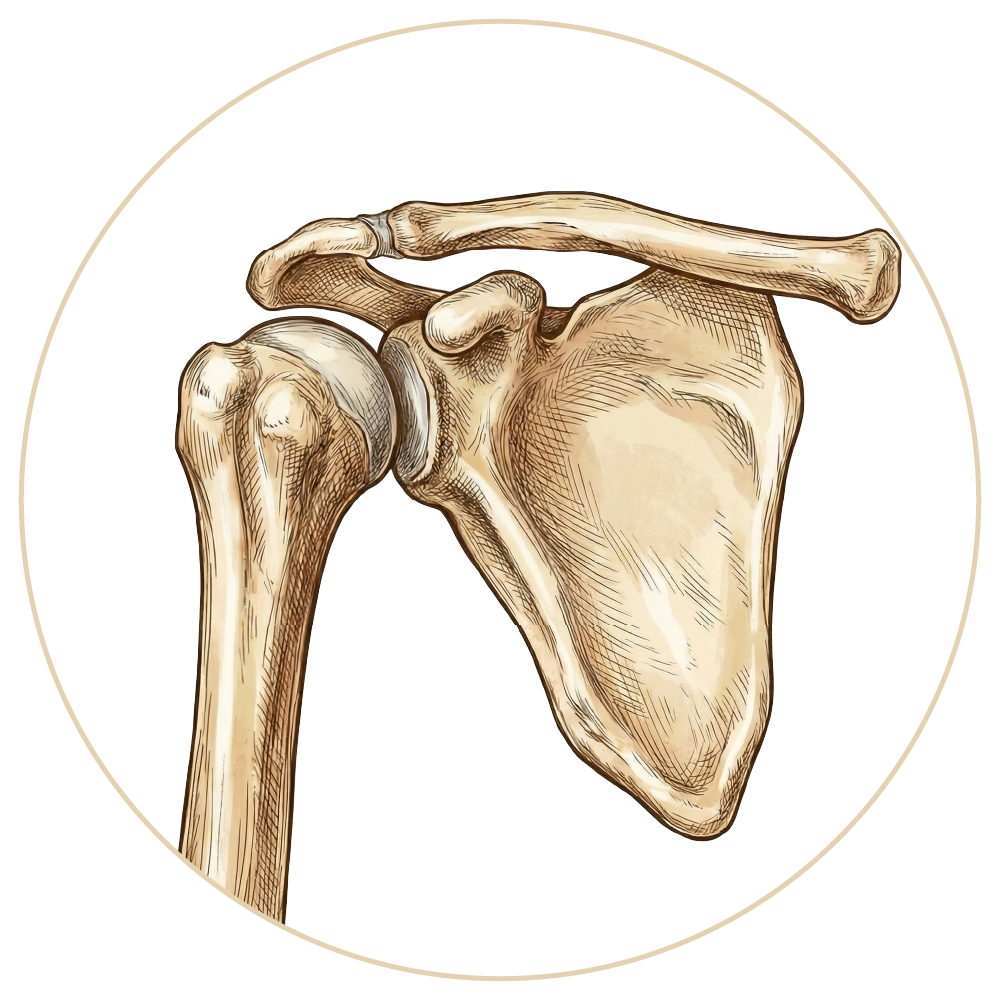

Omuz Hastalıkları ve Tedavileri

Omuz Çıkığı

Omuz Hastalıkları

Rotator Manşet Yaralanmaları